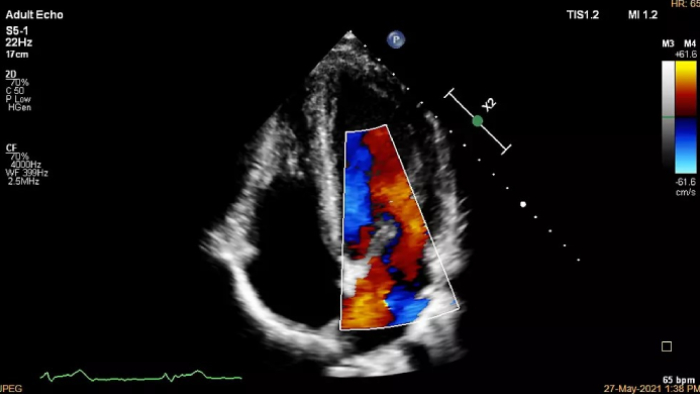

We thank all who were able to attend this year’s European Society of Cardiology programs, including the hands-on workshop sessions, expert symposium on innovations in cardiac imaging workflow, and a friendly open echo skills competition using LifeTec’s Cardiac BioSimulator, the new Philips Compact Ultrasound 5500CV system and Philips Collaboration Live tele-ultrasound.

You can still access recordings of 4 full days of hands-on workshops about best practices in multimodality cardiac imaging with expert teams. See first-time-right imaging for cardiac care, including valvular and related diseases, cardiomyopathies, and intracardiac masses and cardiac tumors.